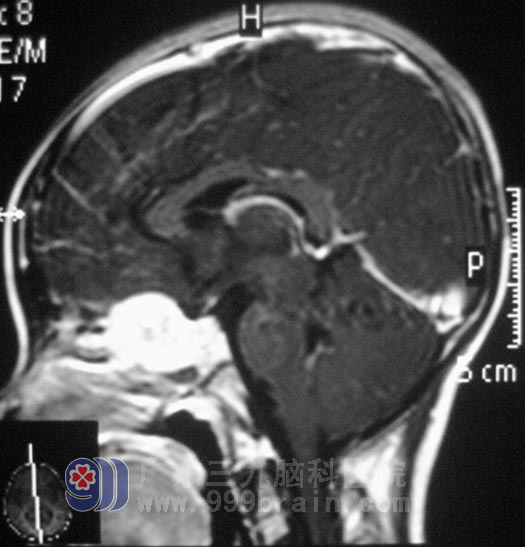

MR检查提示鞍区巨大占位性病变,大小约25.6mm×29.2mm×28.5mm,压迫视神经及周围组织。眼科专家会诊,小宛双眼均无光感,瞳孔直径约5.0mm,双眼对光反射消失。鲁明主任考虑到小宛起病急,视力巨降,经过缜密的准备后,9月22日在全麻下行经鼻蝶鞍区肿瘤切除术,术中暴露蝶窦后见灰白色肿瘤,质韧,不易剔除,血供丰富,蝶窦内、鞍底骨质破坏,在显微镜下予肿瘤切除。术后小宛的瞳孔恢复正常,没有头痛不适,已经转入放疗科行进一步治疗。术后病理结果为:(鞍区)腺泡状横纹肌肉瘤并大面积坏死。http://www.999brain.com/

▲手术前